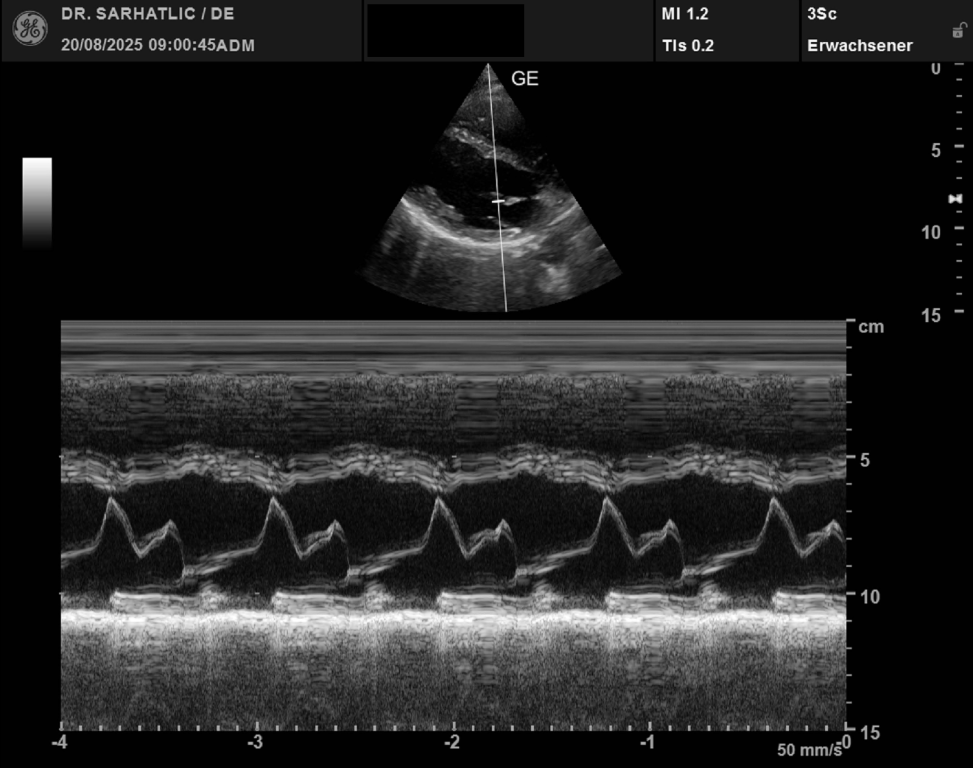

- Ultraschall des Herzens (Echokardiografie)

VORSORGE-SCHWERPUNKTE- Herz- & Kreislauf-Vorsorge